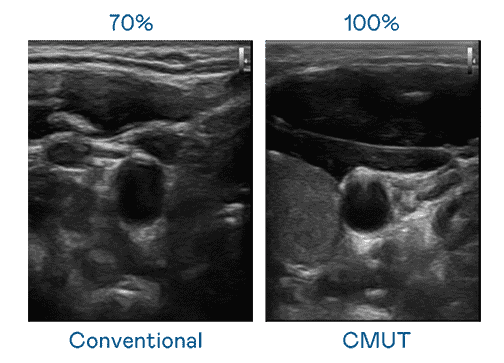

CMUT 技术是一种用电容式微机电元件来产生超音波讯号的技术。。。。与传统 PZT 压电式技术相比,,,CMUT 频宽增加 30%,,,更宽频的超音波讯号让影像解析度大幅提升,,,,是实现高影像品质医疗超音波扫描、、促进精准医疗发展的关键技术。。。。

大频宽带来超清晰影像

超音波影像的解析度高低,,,首先取决于探头能发出的讯号频宽。。冰球突破 CMUT 可提供高清晰的超音波讯号,,,,提供高频宽、、高灵敏度、、、影像纹理细节更高的超音波影像,,协助医护人员缩短影像判读时间及利用精准的医疗影像进行诊断。。。。